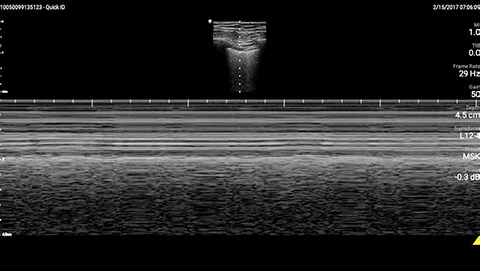

M-mode demonstrating lung sliding